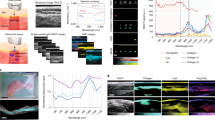

Phantom imaging reveals optoacoustic properties of glycogen

To identify a possible specific glycogen spectrum, we first aimed to determine whether we could visualize its spectrophotometric absorption. An increase in glycogen concentration did not change the specific peak of the photometric spectrum with the investigated wavelengths (Fig. 1A). We could observe an increase of absorption starting from 910 nm, as described in the literature for H2O39. After subtracting H2O background, there is a flat spectrum curve remaining, with only an absolute absorption shift between 2% and 7% glycogen (Fig. 1B). In contrast, D2O does not show an increase of absorption within the observed wavelengths (Fig. 1C) and after subtraction of D2O background it showed similar curves as compared to H2O experiments (Fig. 1D), which indicates no specific spectrophotometric absorption of glycogen.

A Photometric absorption spectra between 700 and 980 nm for pure H2O, and H2O with 2% and 7% glycogen, respectively (left). Photometric absorption spectra with subtracted H2O background (right). B Photometric absorption spectra between 700 and 980 nm for pure D2O, and D2O with 2% and 7% glycogen, respectively (left). Photometric absorption spectra with subtracted D2O background (right). C Averaged optoacoustic signal in the preclinical imaging system from 700 to 1100 nm for pure H2O, pure D2O, and 2% glycogen in H2O and D2O, respectively. D Averaged optoacoustic signal in the clinical imaging system from 700 to 1100 nm for pure H2O, pure D2O, and 2% glycogen in H2O and D2O, respectively. E Averaged optoacoustic signal in the clinical imaging system from 700 to 1100 nm for pure minced meat and minced meat of the same origin with increasing glycogen concentrations. Values are given as mean values of scan data with negative signal intensities set to 0 or given as mean values of the top 10% of signal intensities per scan. The data represent one of two independent experiments with similar results. This figure was created with BioRender.com released under a Creative Commons Attribution-NonCommercial-NoDerivs 4.0 International license.

To examine the optoacoustic properties of glycogen, we used a preclinical imaging system designed for small animal imaging40. Using this setup, H2O and 2% glycogen in H2O were detected, while D2O and 2% glycogen in D2O had no specific signal increase (Fig. 1E). Next, we transferred this to a clinical imaging system28,41, which detected higher signal values when glycogen was added into H2O, especially starting at 910 nm and a pronounced peak at 980 nm (Fig. 1F). The H2O, D2O and glycogen in D2O showed similar curve progression. To validate the transferability of our in vitro glycogen findings into an actual muscle, we developed an ex vivo muscle phantom. Using a 3D-printed mold filled with minced meat, we started diluting it in H2O and successively added glycogen. We increased the glycogen content in 50% steps in relation to the calculated concentration in pure meat and imaged it using the clinical system. Our comparison shows an increasingly higher signal over several single wavelengths (SWLs), including 830 nm, 850 nm, 980 nm, 1030 nm, and 1080 nm for increasing concentrations of glycogen (Fig. 1G, H). This suggests that glycogen, although not detectable as a pure substance, offers an optoacoustic imaging target in the clinical setting due to its potentially high-water binding capacity.

MSOT enables visualization of biceps muscle involvement

For all subjects, MSOT imaging was completed, and data was post-processed using two independent scans of each biceps muscle for the final analysis. In total, n = 80 scans (n = 40 of HV, n = 40 of LOPD) were included, and signals, both SWLs and MSOT parameters (MSOT-derived lipid signal, MSOTlip; MSOT-derived collagen signal, MSOTcol), were compared between groups. Figure 4A shows exemplary imaging results. Given the heterogeneity of the disease manifestation, each muscle was regarded as an individual data point. Therefore, n = 20 matched muscle regions were compared. The optoacoustic spectrum derived from 12 SWL showed overall higher values for PD patients compared to HV (Fig. 4B). MSOTlip provided better performance to distinguish HV from LOPD than clinical parameters (body mass index, BMI) or fat fraction derived by MRI (Fig. 4C). Spectral unmixing derived higher MSOTcol (1727 ± 555.5 arb.units vs. 2152 ± 674.0 arb.units, P = 0.0029), MSOTlip signals (1267 ± 356.6 arb.units vs. 2713 ± 1732 arb.units, P < 0.0001), while in this approach SWL (800, 930, 980 nm) signals remained unchanged (Fig. 4D–H). However, the exact measure also depends on the proportion of the signal that is quantified (Supplementary Figs. 1–4). By separating patients with regard to disease severity based on QMFT, one can observe decrease of MSOTcol and increasing MSOTlip quantification, possibly resembling the fibro-fatty degeneration of the muscle (Fig. 4I, J). MSOTlip demonstrated the strongest correlation to the other investigated clinical standard assessment (Fig. 4E).

A From left to right: representative MSOT imaging quantification representing anatomic information (RUCT), unspecific tissue/muscle signal (SWL 800 nm), MSOTcol and MSOTlip. Disease severity of HV vs. LOPD (mildly, moderately and severely) is increasing from top to bottom cases. B Comparison of MSOT spectral signal values of HV and LOPD patients from 700 to 1100 nm. Each dot represents the mean of a whole proband group (HV = green, LOPD = violet), bars represent 95% CI. Results represent 80 datasets from n = 40 independent biceps muscle regions (n = 20 HV/n = 20 LOPD) in n = 20 biologically independent subjects (n = 10 HV and n = 10 patients with LOPD). C ROC Curve of Top 10% signals MSOTlip, BMI values and MRI fat fraction values to distinguish HV and LOPD muscles. n = 40 independent muscle regions (n = 20 HV/n = 20 LOPD) in n = 20 biologically independent subjects (n = 10 HV and n = 10 LOPD). Comparison of Top 10% of signal intensity for SWL 800 nm (D), 930 nm (E), 980 nm (F), MSOTcol (G), MSOTlip (H) between HV and LOPD patients with individual scans as individual data points. Results represent 80 datasets from n = 40 independent biceps muscle regions (n = 20 HV/n = 20 LOPD) in n = 20 biologically independent subjects (n = 10 HV and n = 10 patients with LOPD). Each bar displays the mean of top 10% MSOT signal of the biceps muscle of a whole proband group with the error bars indicating SD (green bar/dots = HV and violet bar/dots = LOPD). MSOT signal comparison for different LOPD severity (HV = black, mild = pink, green = moderate, severe = purple) for MSOTcol (I) and MSOTlip (J). Results represent 80 datasets from n = 40 independent biceps muscle regions (n = 20 HV/n = 20 LOPD) in n = 20 biologically independent subjects (n = 10 HV and n = 10 patients with LOPD). Each filled dot shows the mean of top 10% signal of the biceps muscle of different severity groups and HV (black dots = HV = QMFT = 64, pink dot = mild LOPD = QMFT 64–49, green dot = moderate LOPD = 48–33, purple dot = severe PD = 32–0). Statistical difference was tested with Welch’s t-test. K Correlation matrix for maximum MSOT signal intensity of SWL 800 nm, 930 nm, 980 nm and MSOTcol and MSOTlip correlated to reference clinical parameters including FVC%, FEV1%, BMI, 6MWT, QFMT, ultrasound greyscale levels, fat fraction. Correlations are indicated in the color range from highly negative (blue) to low negative/positive (green) to highly positive (yellow). Correlations are given by Spearman correlation coefficient (rs), two-tailed test. P ≤ 0.05 was considered statistically significant. n = 20 biologically independent subjects (n = 10 HV/n = Confidence interval was 95% 10 patients with LOPD). HV healthy volunteer, LOPD late-onset Pompe disease patient, MSOT multispectral optoacoustic tomography, RUCT reflected ultrasound computed tomography, ROC receiver operating characteristic curve, FVC functional vital capacity, FEV1 forced expiratory volume, BMI body mass index, 6MWT 6-min walking test, QMFT quick motor function test.